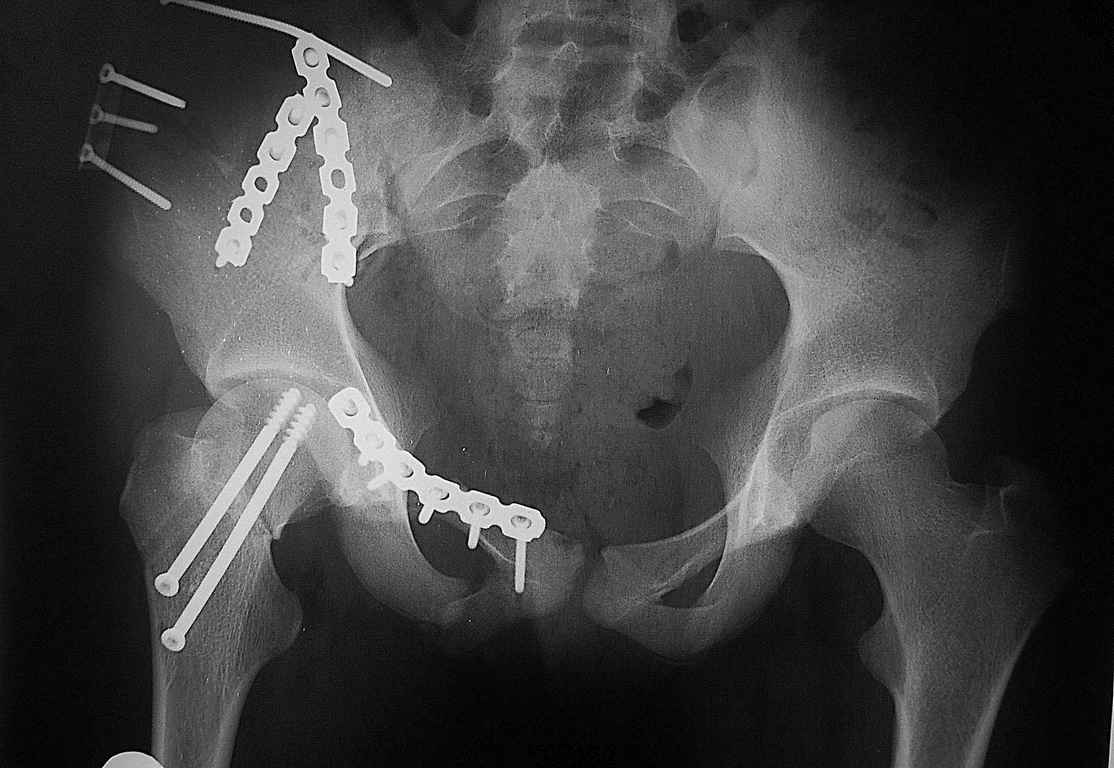

Re: Перелом костей таза

Уважаемые коллеги огромное спасибо за советы! Больная была прооперирована А.В.Рунковым.